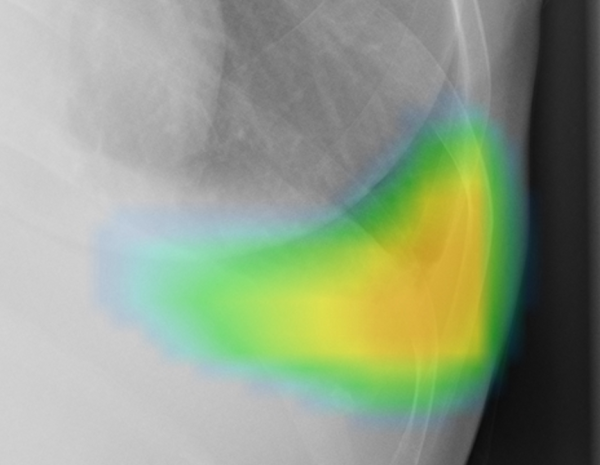

ヒートマップ/輪郭表示機能

異常所見の存在可能性(確信度)を、青から赤へのグラデーションで示すヒートマップ表示について、多くの利用者からご好評いただいている。一方、モノクロモニタを利用する一部の読影環境では、淡いヒートマップが確認しにくいという課題があった。新バージョンでは、異常所見の疑われる領域の表示方法として、「ヒートマップ表示」「輪郭表示」「ヒートマップと輪郭の併用表示」の3つの表示パターンが選択可能になった。これにより、各施設の運用環境に応じた最適な表示方法を利用できる。